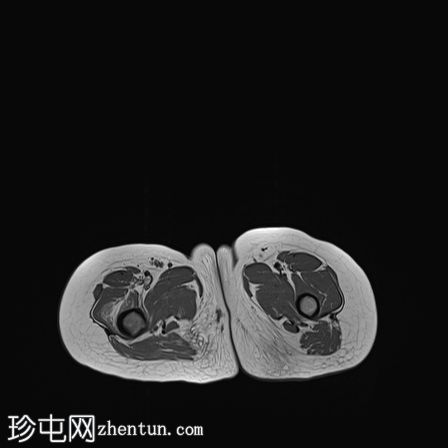

CT

在右股骨近端后外侧皮质内可见一小的透亮病灶,周围有中度硬化。内部无钙化。

结合患者的年龄、临床表现及放射学表现,该病例为典型的骨样骨瘤。